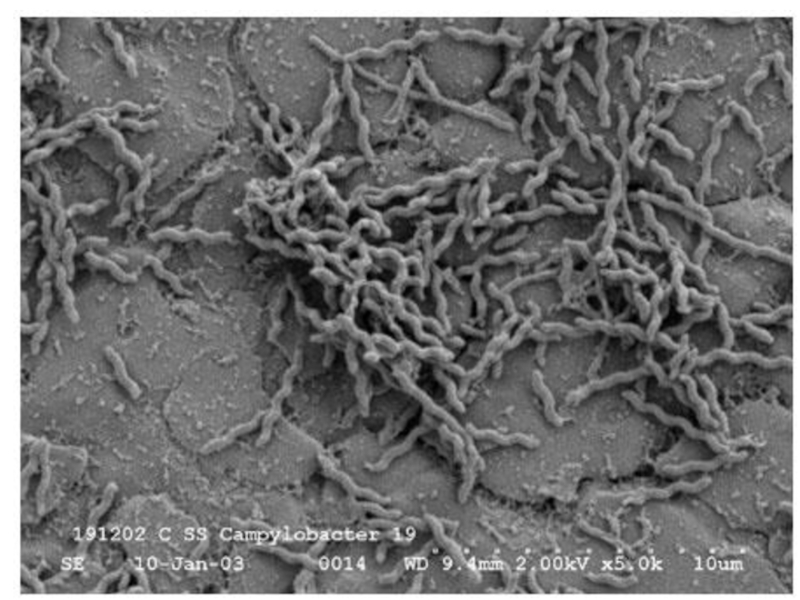

Кампилобактер фетус: патогенез и инфекции

Раздел: Другие животные